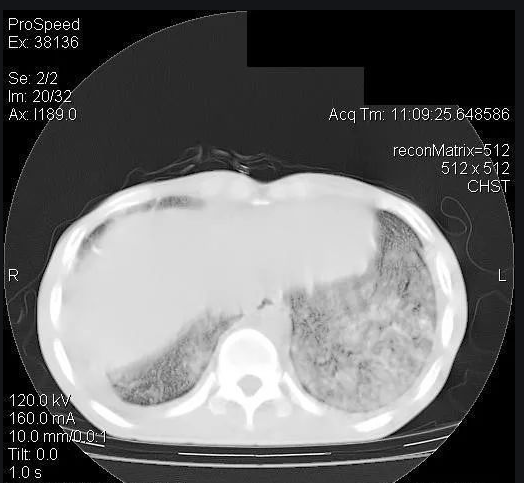

正常情况下,拍摄CT和X光片时,我们的肺在影像片上显示是黑色的。这是因为肺里面是我们吸入的空气,空气容易被X光穿透。所以,正常的肺在X线下,看起来是黑色的。如果肺里有炎症、有液体渗出,或者有占位性病变、有实变,导致肺内的气体减少,拍片的时候,X光不容易透过去,整个肺看起来就可能是白色的。这类患者往往病情危重,有生命危险,专业术语称为重症肺炎,俗称“大白肺”。

新冠肺炎病情恶化时,会出现以深部气道和肺泡损伤为特征的炎性反应。大量炎性渗出以及肺的实变,就会出现“大白肺”的情况。也就是说,新冠肺炎重症的患者肺里有较多黏液分泌物,这些分泌物将小气道堵塞,气体就无法进入到肺内。临床上的主要症状是患者会感到明显的缺氧,呼吸费力,经手指末梢测得的血氧饱和度逐步下降,随病情加重直至呼吸衰竭而死亡。